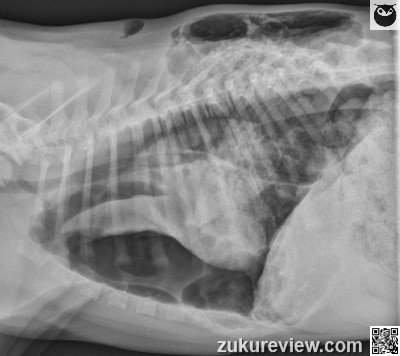

This puppy has a pneumothorax and needs immediate thoracocentesis and chest tube placement. The left hemithorax appears gas distended with marked rightward mediastinal shift.

A large, loculated area of subcutaneous emphysema is seen over the caudal dorsolateral thorax; however, a communication with the thoracic cavity or the external body wall cannot be identified.

A triangular wedge of soft tissue opacity is seen in the mid left thorax and is consistent with collapsed left lung.

A smaller, poorly demarcated area of increased soft tissue opacity is also seen superimposed over the 10th left rib adjacent to the body wall at the level of the most severe subcutaneous emphysema. There is mild pleural effusion in the right hemithorax.

The right pulmonary parenchyma is difficult to evaluate, but appears to be within normal limits. The musculoskeletal structures appear within normal limits.

This is severe left sided tension pneumothorax with collapse of the left lung lobes.